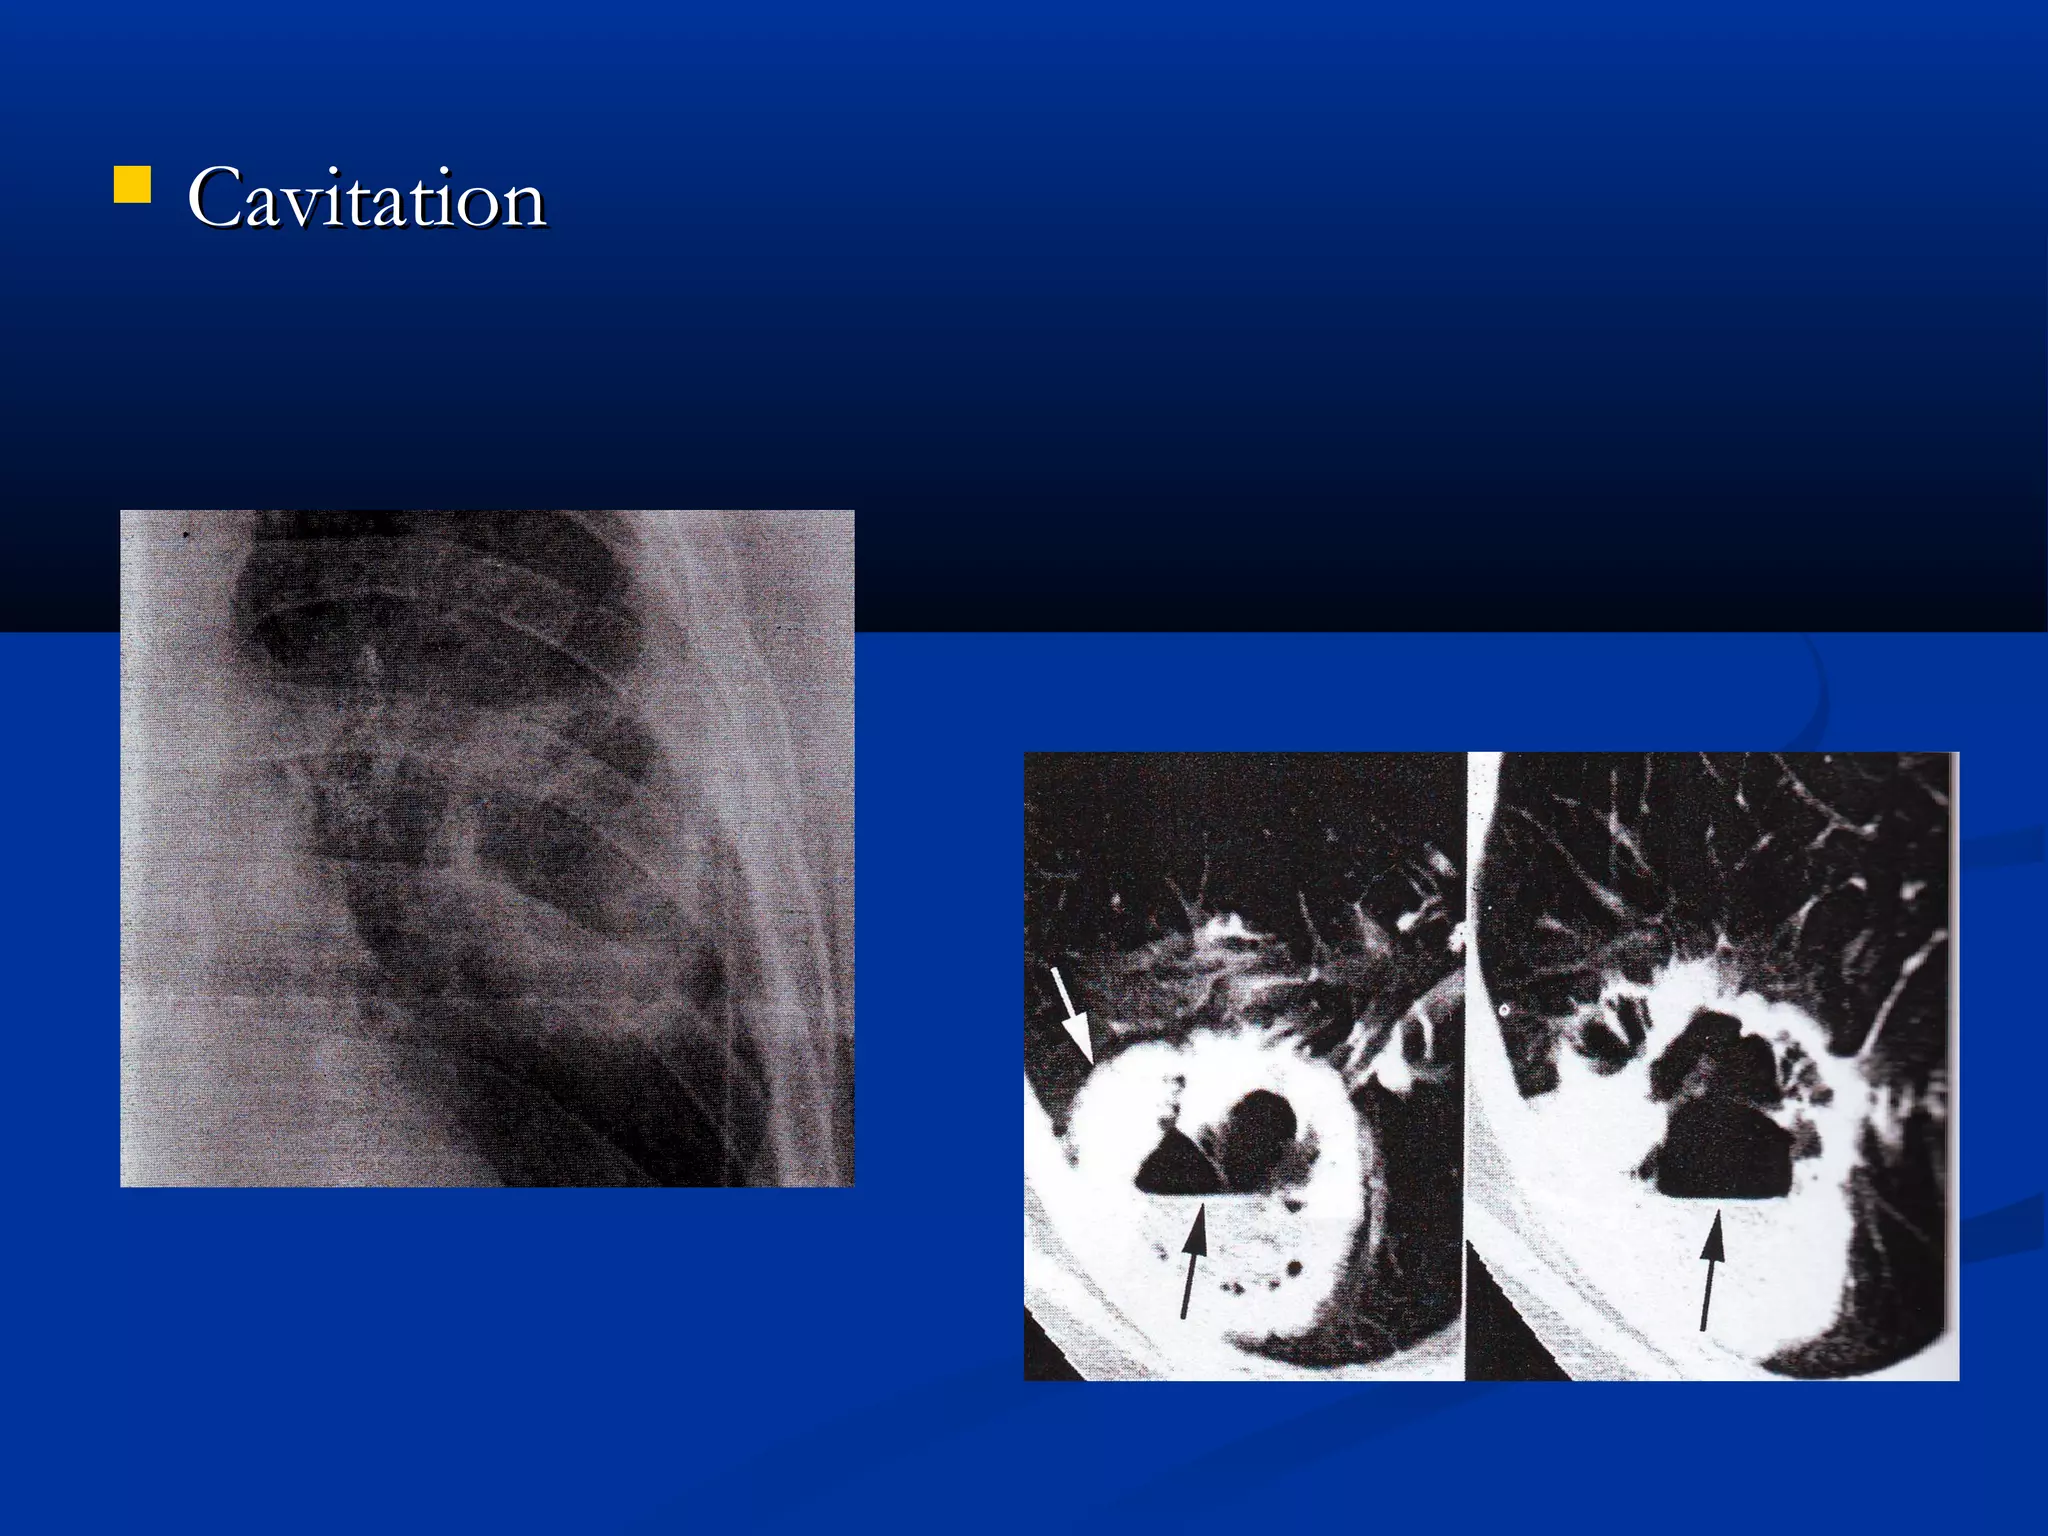

   Cavitation

Cavitation